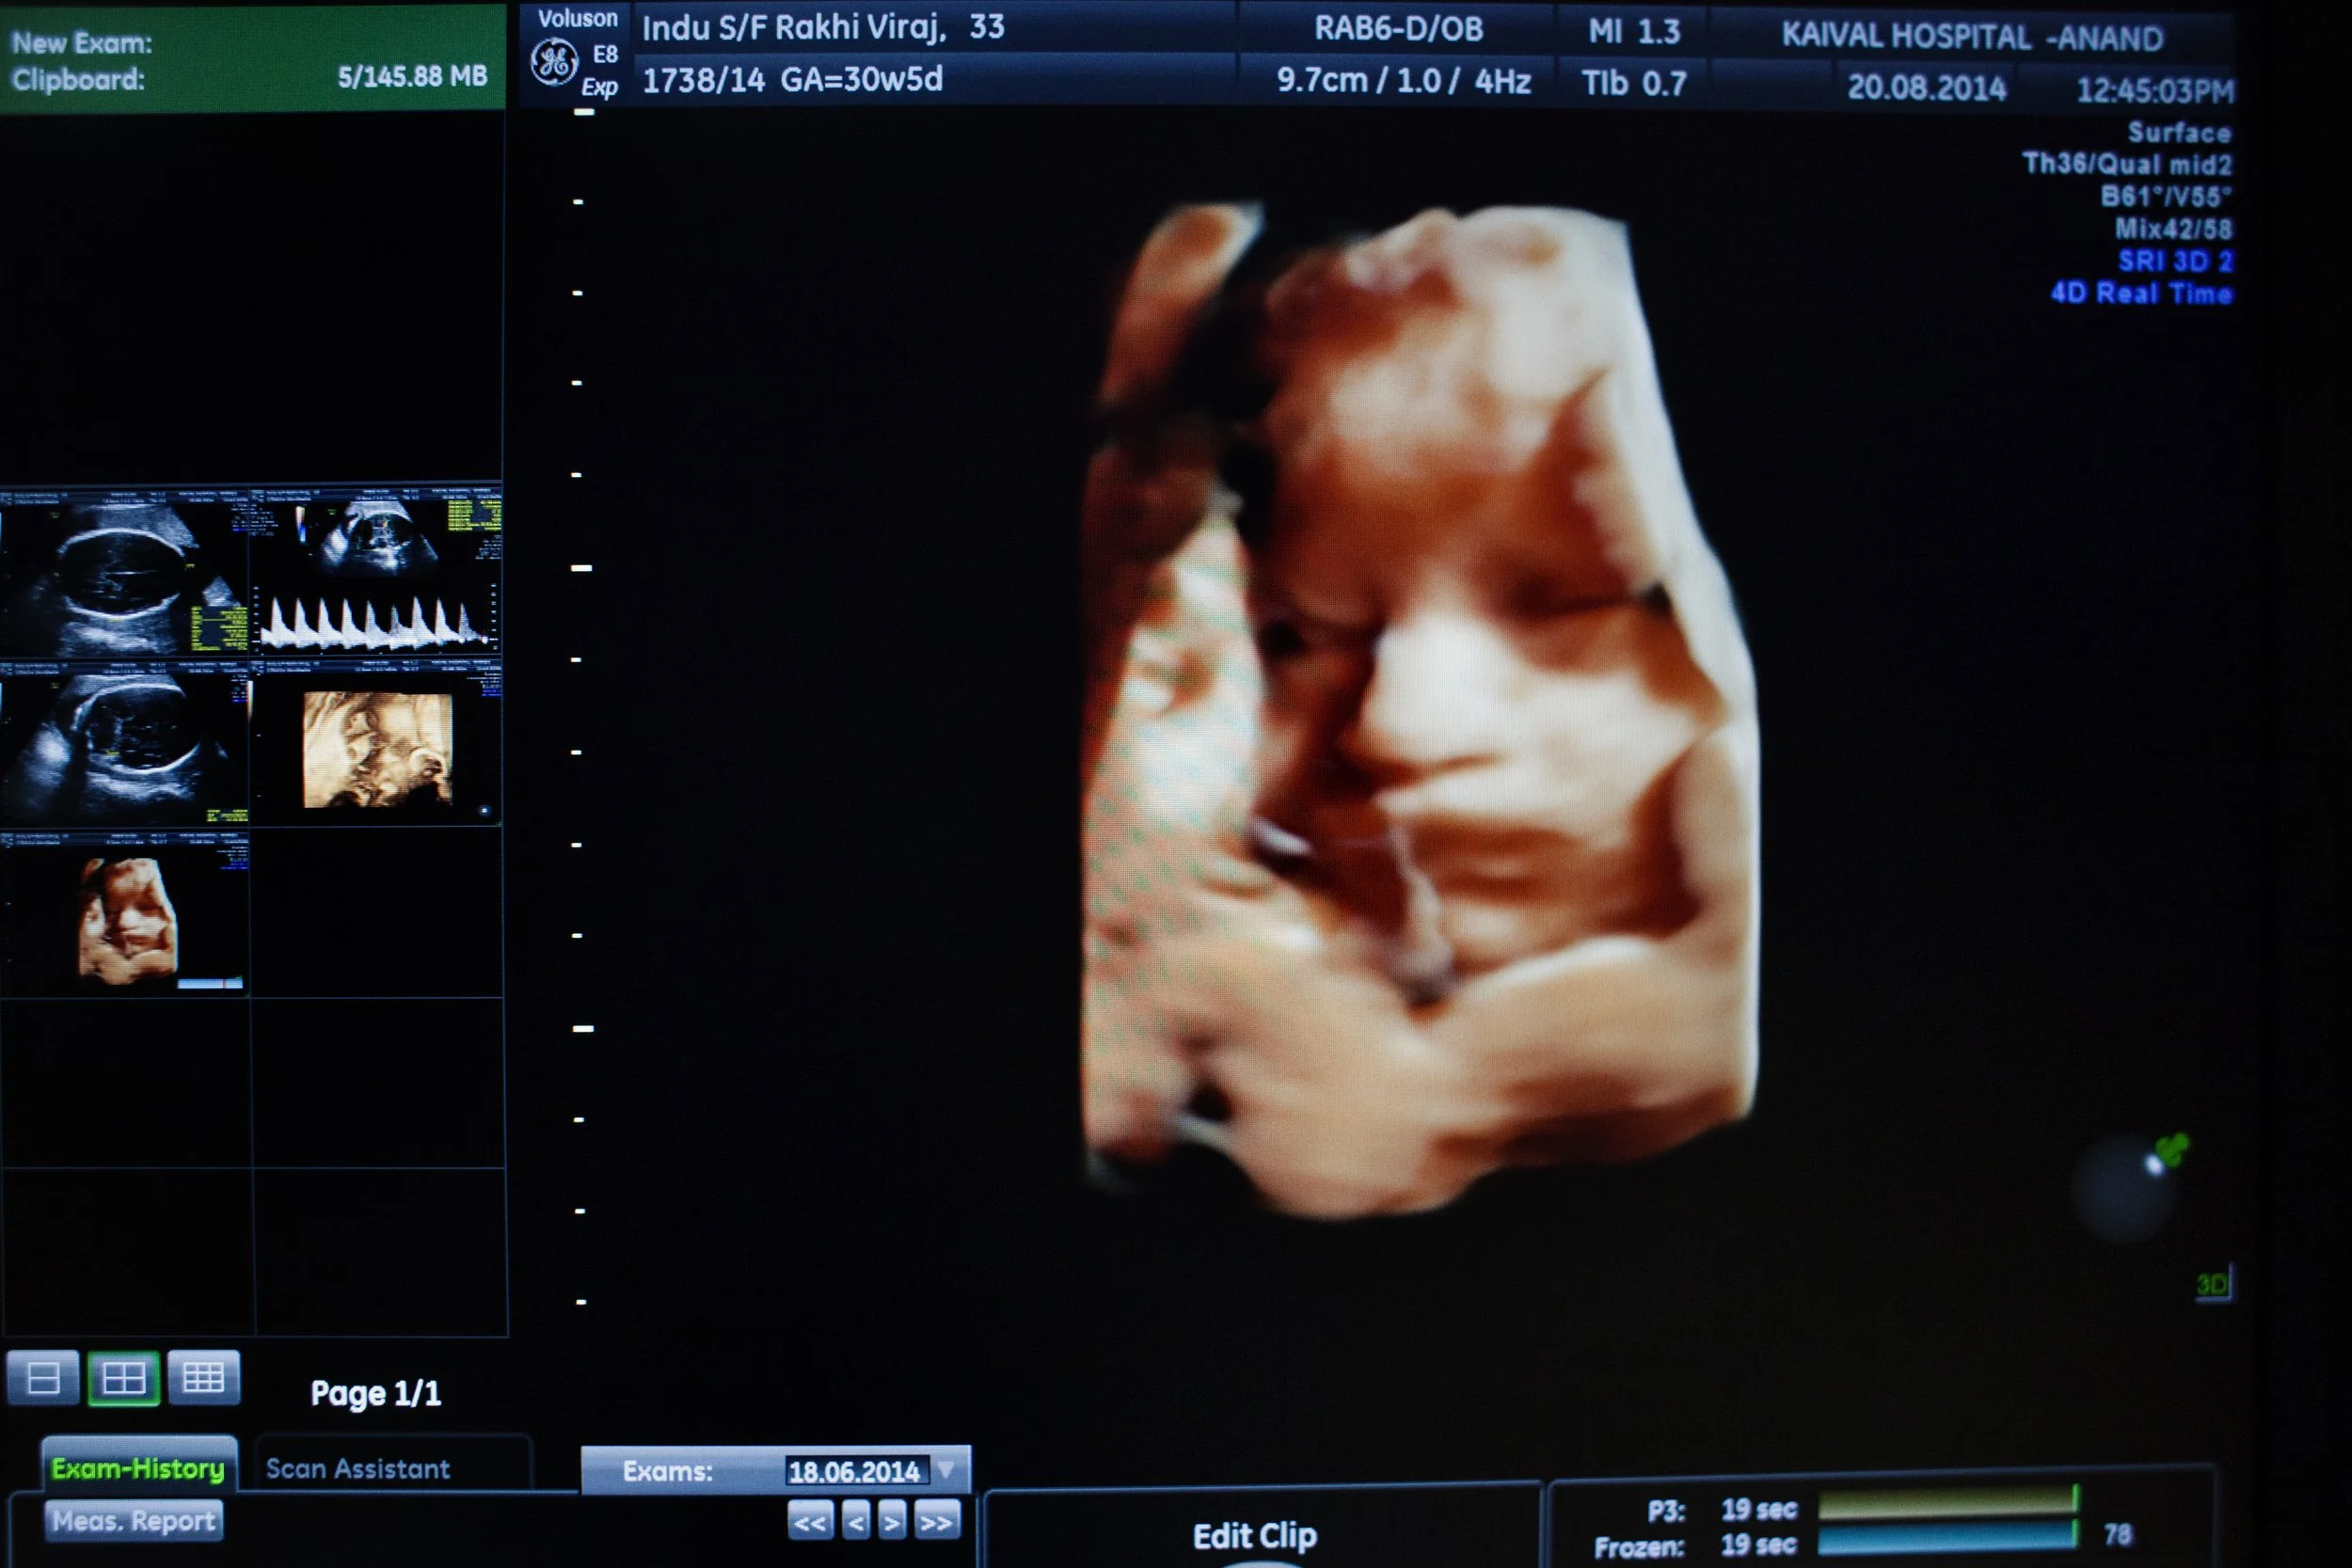

In 2003 Dr Nayna Patel, a fertility specialist, had the first case of surrogacy. She treated an infertile couple to have their own child with the help of the woman’s mother as a surrogate. From that case in the Akanksha Infertility Clinic were born 818 children with 612 deliveries, according to the latest data on August.

This program give to the infertility couple the opportunity to pay to have their own child and, at the same time, to improve the life of the poorest Indian women.